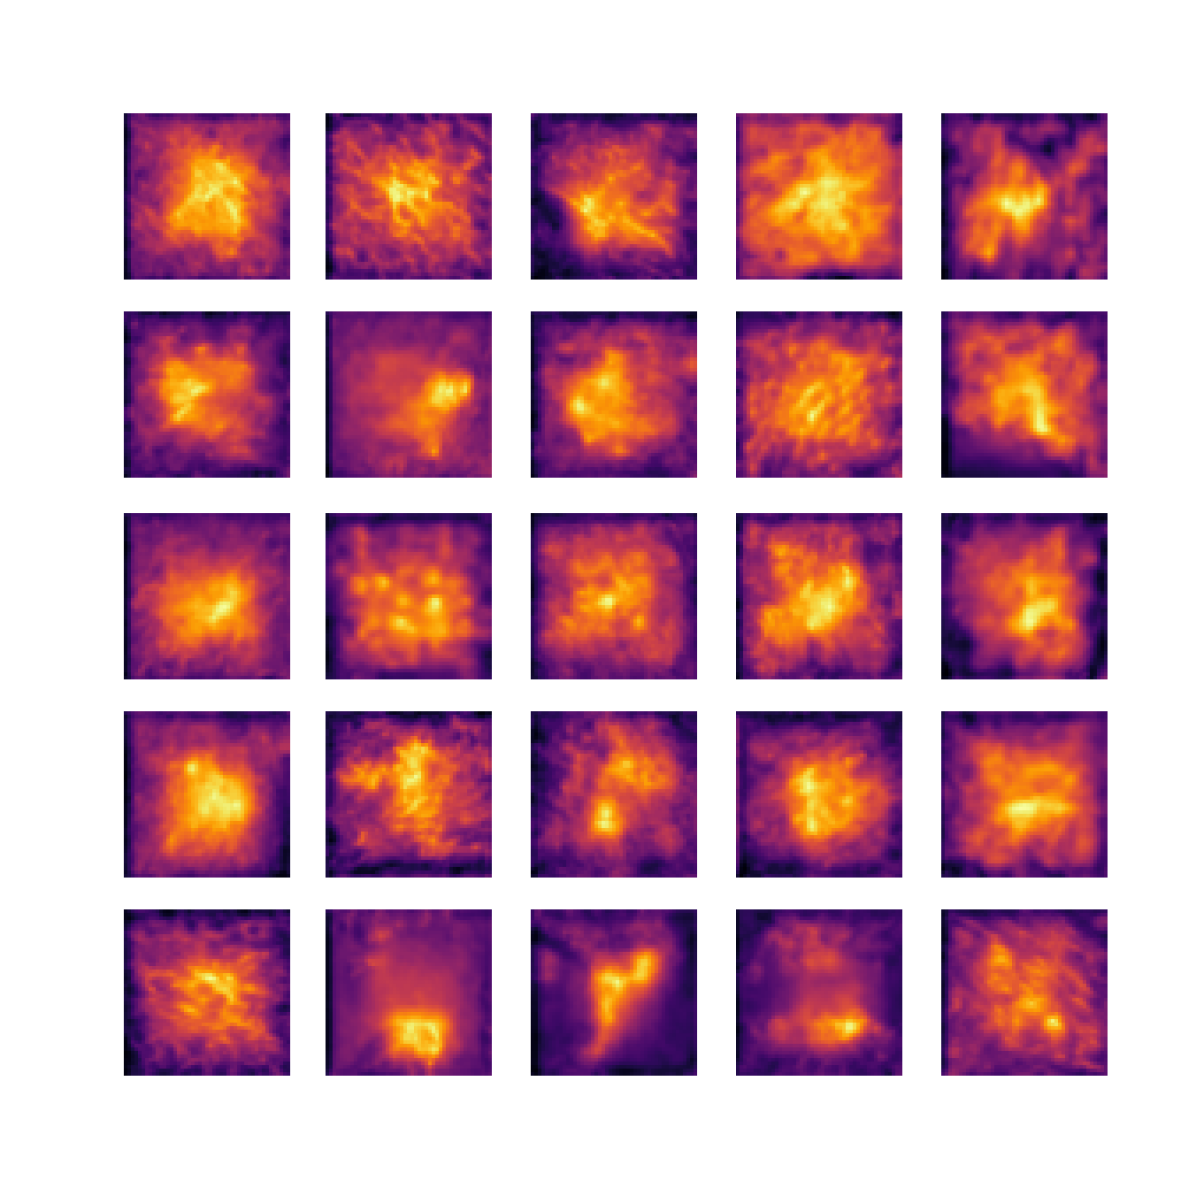

We also analyse the activation maps for each model using GradCAM as described in section S3. This offers more insight into the areas of the image which are contributing most heavily to the models’ representations. In Figure 4(b) we present some representative examples, however, a larger selection which was chosen at random is presented in Figures S10 to S25. The larger selection makes it easier to see the emergent patterns, including that privileged Siamese models tend to mainly identify features which are strongly present in both inputs, while unprivileged Siamese models tend to learn more diffuse features that are not specific to one cell phenotype or image region. TriDeNT ♆ incorporates both sets of features, learning both features specific to the privileged data and more the general features associated with unprivileged Siamese networks.

We can see in Figure 4(b) panel A that for ERG, the privileged Siamese model focuses almost exclusively on any nuclei which could be endothelial cells. As there are very few endothelial cells in the dataset, it could be an effective strategy to identify anything that could potentially be an endothelial cell to minimise the difference between the representations of the H&E model and the IF mask model. In the corresponding unprivileged Siamese image, we see that the model identifies some of these nuclei, albeit less strongly, but also focuses heavily on the other tissue and even the background, while strongly fixating on two spots of debris in the center of the image. This model has less ‘incentive’ to learn the weak features related to endothelial cells as these occur rarely and are not easy to detect, while more generic strong features such as the presence of connective tissue and the prevalence of background are more common and predictable from augmented images. We see that TriDeNT ♆ combines these two feature sets, strongly identifying nuclei while also identifying the connective tissue.

In panel C we see a similar pattern, with the privileged Siamese model fixating solely on the nuclei, while the TriDeNT ♆ model takes a more balanced approach. The unprivileged Siamese model appears to focus on a single cluster of nuclei while neglecting others, and similarly identifies an area of fibroblasts with its distinctive pattern but does not others.

In contrast to panels A and C which represent models with poor privileged Siamese results, panels B and D represent models whose privileged Siamese results were comparable to both TriDeNT ♆ and even the supervised baseline. It is therefore interesting to note that there are far more similarities between the privileged Siamese and TriDeNT ♆ models in both cases. Particularly in panel B, TriDeNT ♆ and the privileged Siamese model return virtually identical heatmaps, with both strongly identifying epithelial nuclei and neglecting the same areas of connective tissue. The unprivileged model in this case appears to focus solely on the centre of the image, giving a significantly different heatmap to the other panels.

Panel D again shows the previous pattern, with the privileged Siamese model identifying the features strongly present in the privileged data – fibroblasts – while neglecting the nuclei present. TriDeNT ♆ also strongly identifies the connective tissue, but, unlike the privileged Siamese model, does not completely neglect the nuclei. The unprivileged Siamese model primarily identifies background, and does not appear to identify the nuclei in this example.